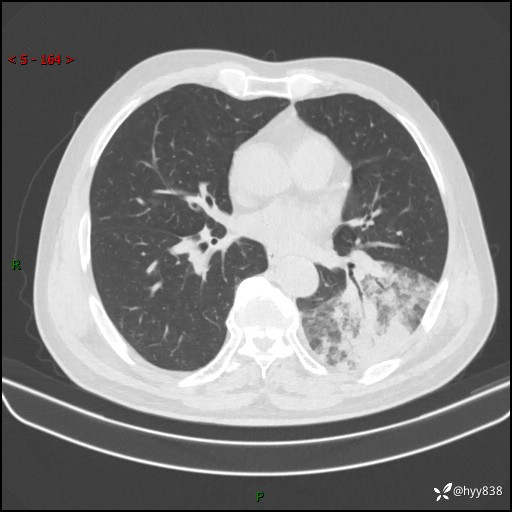

59岁/男,发热伴咳嗽3天。白班偶遇,“大叶性肺炎”,病原体挑战---结果公布~

【患者信息】:59岁/男

【主诉】:发热伴咳嗽3天

【检查】:胸部CT平扫